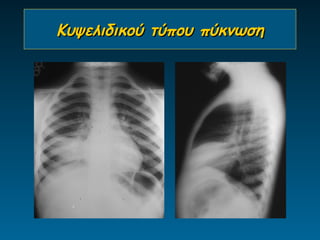

Κυψελιδικού τύπου πύκνωση

•λοίμωξη

βακτηρίδια

μυκόπλασμα

φυματίωση

•πνευμονικό οίδημα

•πνευμονίτιδα

•πνευμονική θλάση

•κυψελιδική αιμορραγία

•παρ’ ολίγον πνιγμός